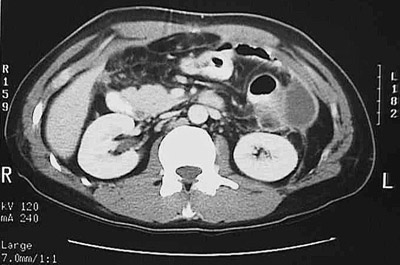

Click on the abdominal abscess in the CT scan above:

This computed tomographic (CT) imaging scan of the abdomen in axial (transverse) view demonstrates an abscess adjacent to the descending colon in a patient who had a ruptured colonic diverticulum.